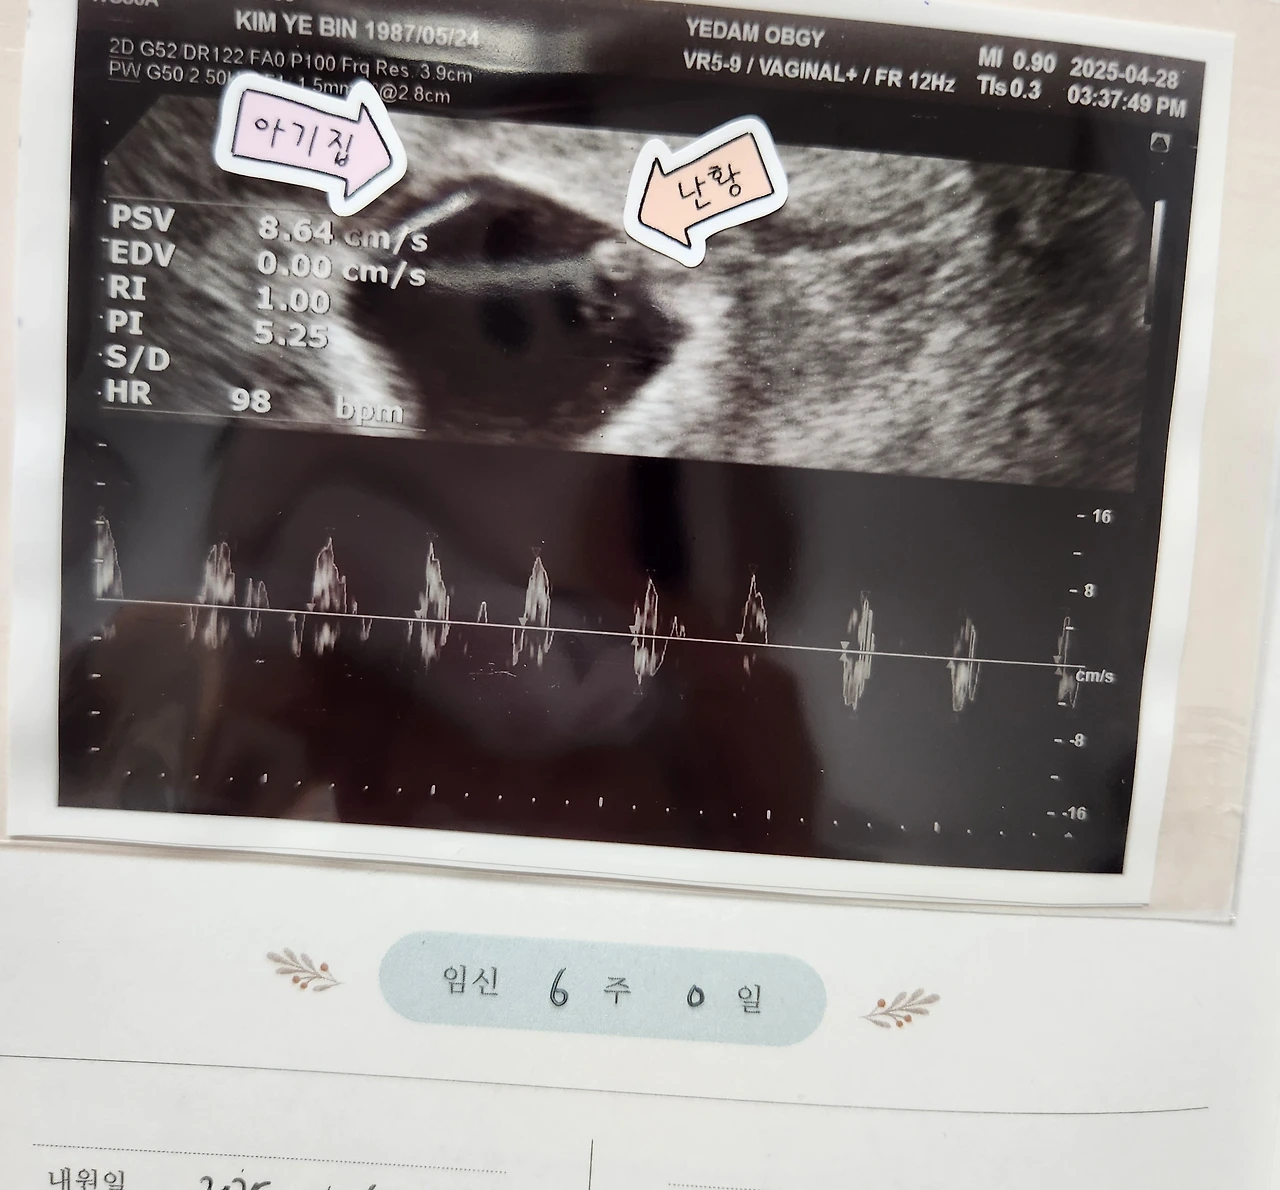

4월 28일. 6주 0일 차.

첫 초음파 듣고 너무 기뻤던.

신테스트기의 두줄을 확인했던 날에도 기뻤지만, 초음파로 심장소리를 듣던 그날은 또 달랐다. 0.3cm 크기의 쪼꼬미가 숨 쉬고 있는데 신기하고 설레고 뭐라 표현해야 할지 모르겠다.